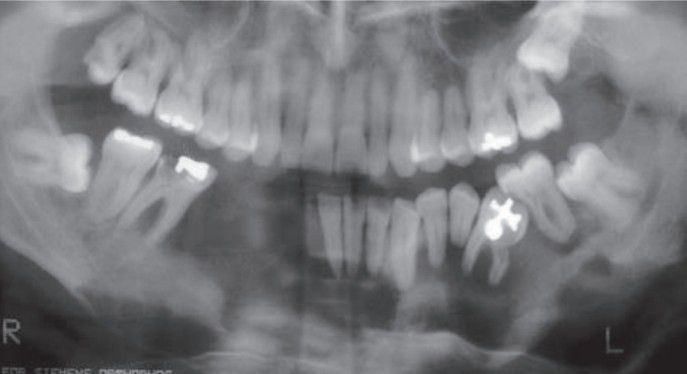

Langerhans cell disease

Langerhans cell disease resulting in marked destruction of mandible